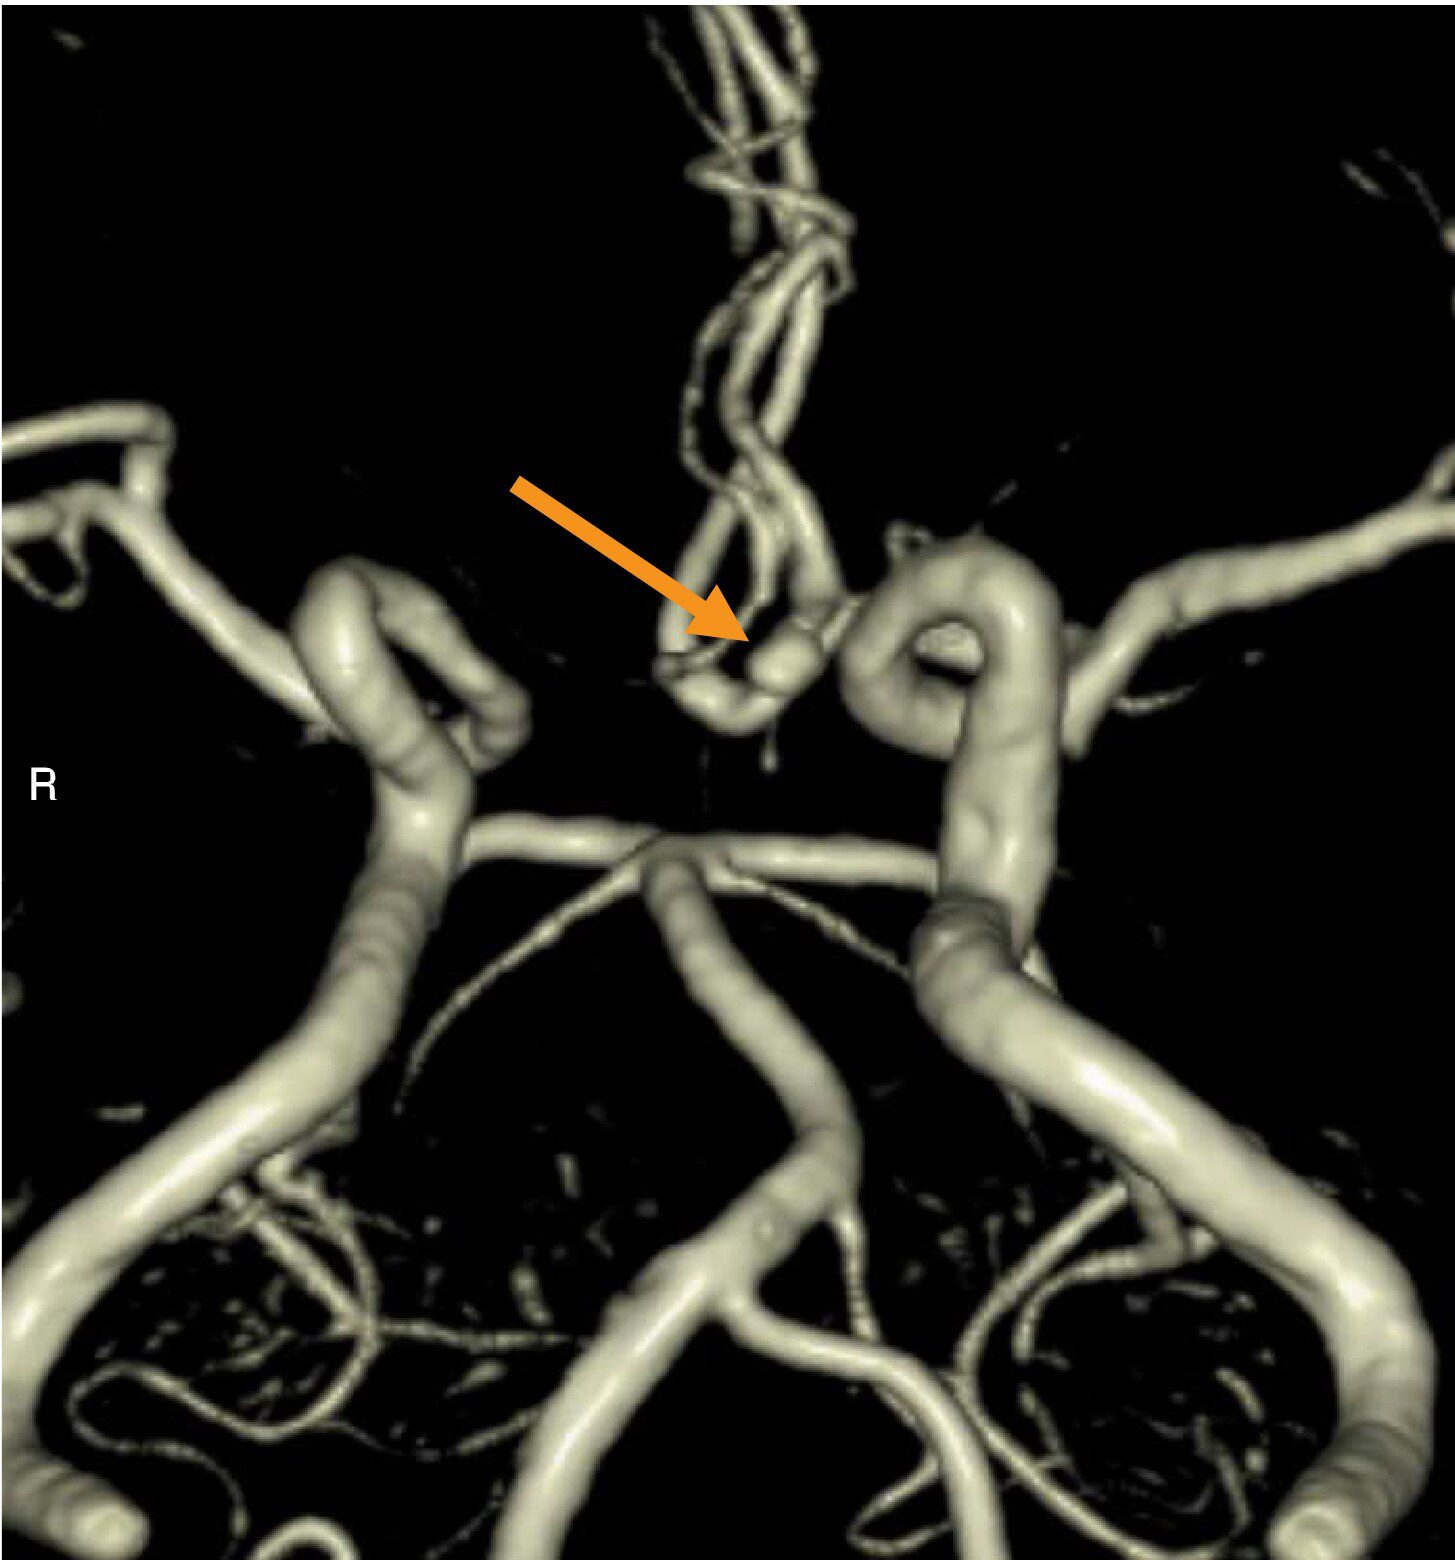

頭部MRAのMIP像(別冊No.3A)及び3D再構成像(別冊No.3B)を別に示す。矢印で示す動脈瘤の部位はどれか。

- 1脳底動脈

- 2後交通動脈

- 3後大脳動脈

- 4前交通動脈

- 5中大脳動脈